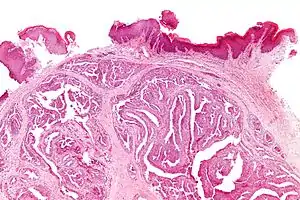

| Micrograph of a papillary hidradenoma with papillary structures; fragmented overlying epidermis is at the top of the image. H&E stain. | |

Microscopic histopathological analyses of papillary hidradenoma tumors typically reveal a nodule in the dermis, i.e. layer of skin between the epidermis and subcutaneous tissue. The tumor consists of complex patterns of interconnecting tubular and papillary (i.e. thin finger-like or frond-like) structures.[19] These structures are lined with glandular epithelial and myoepithelial cells. The glandular epithelial cells appear to be excessively proliferating in the ducts leading to the epidermis and show oxyphilic changes, (i.e. cytoplasm filled with large mitochondria, glycogen, and ribosomes) while the myoepithelial cells often appear clear cell-like, i.e. have uncolored cytoplasm when stained with hematoxylin and eosin.[1] The histopathology of anogenital and ectopic papillary hidradenomas are similar to each other.[7][9][15][18]